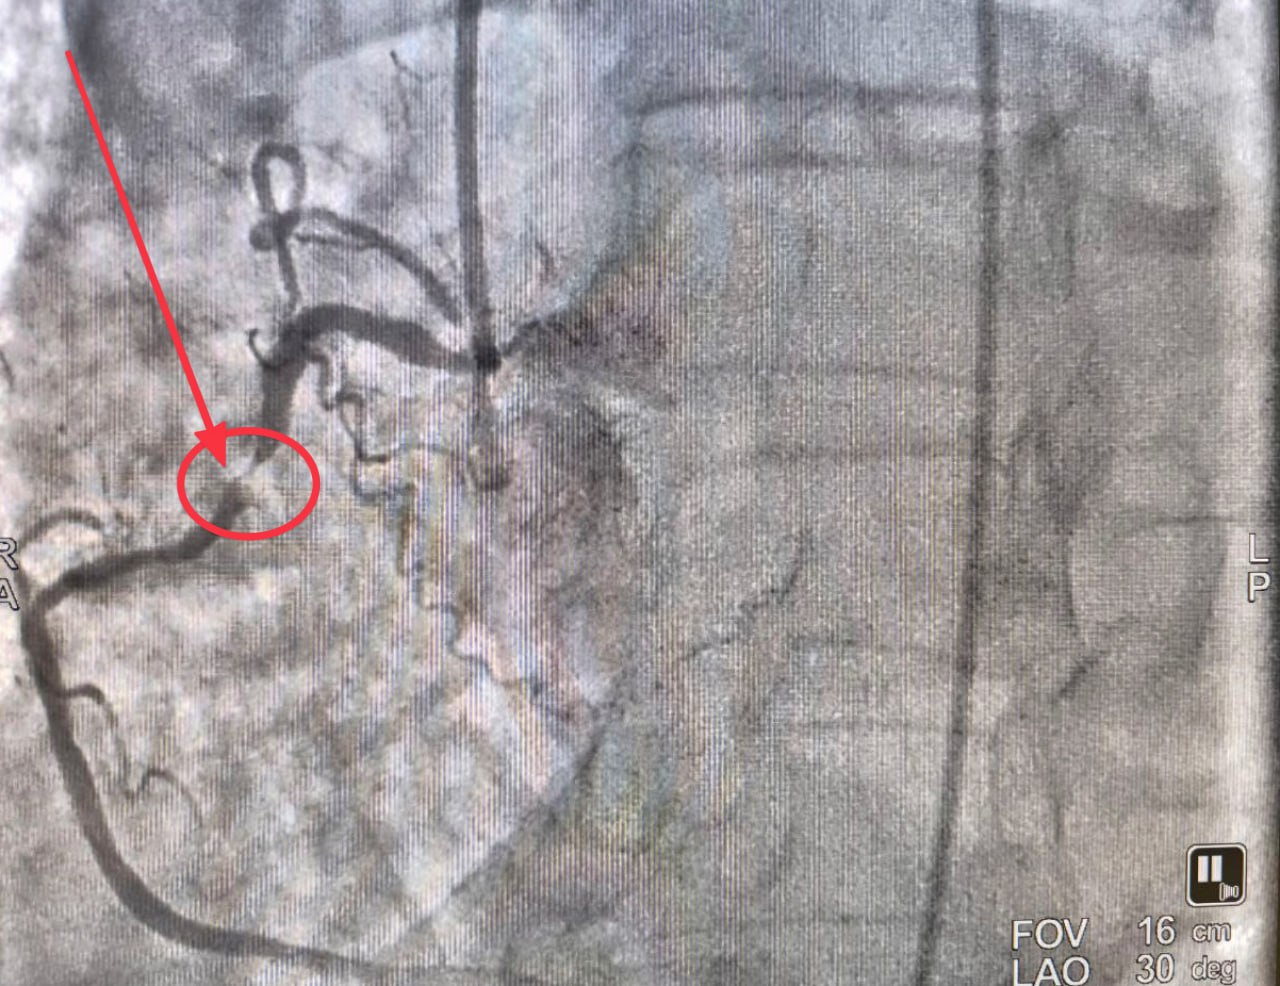

Команда кардиологов, рентгенхирургов и анестезиологов-реаниматологов провела экстренную баллонную ангиопластику и стентирование коронарной артерии. Цель — восстановить кровоснабжение сердца и минимизировать последствия инфаркта.